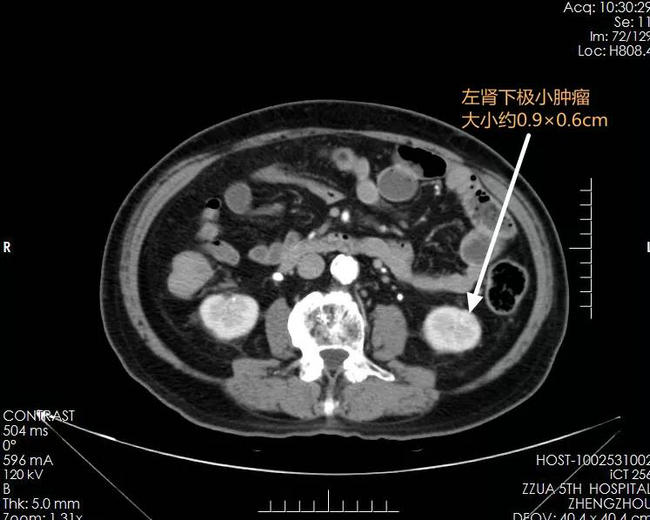

▲ 术前影像检查资料:左肾肾窦处中央型肾癌,左肾下极小肿瘤;双肾萎缩,形态失常(高血压、糖尿病靶器官损害表现)